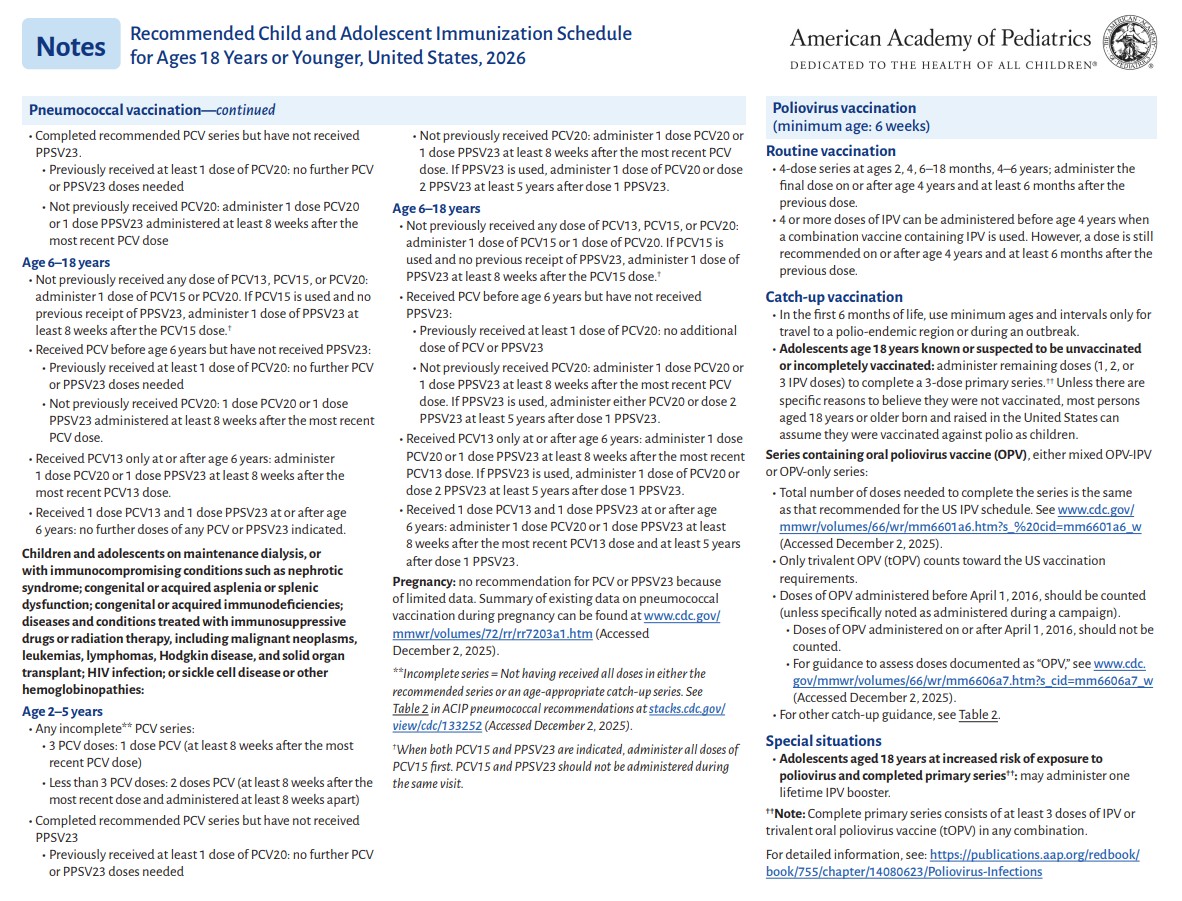

p 13

p 14

p 15

p 16